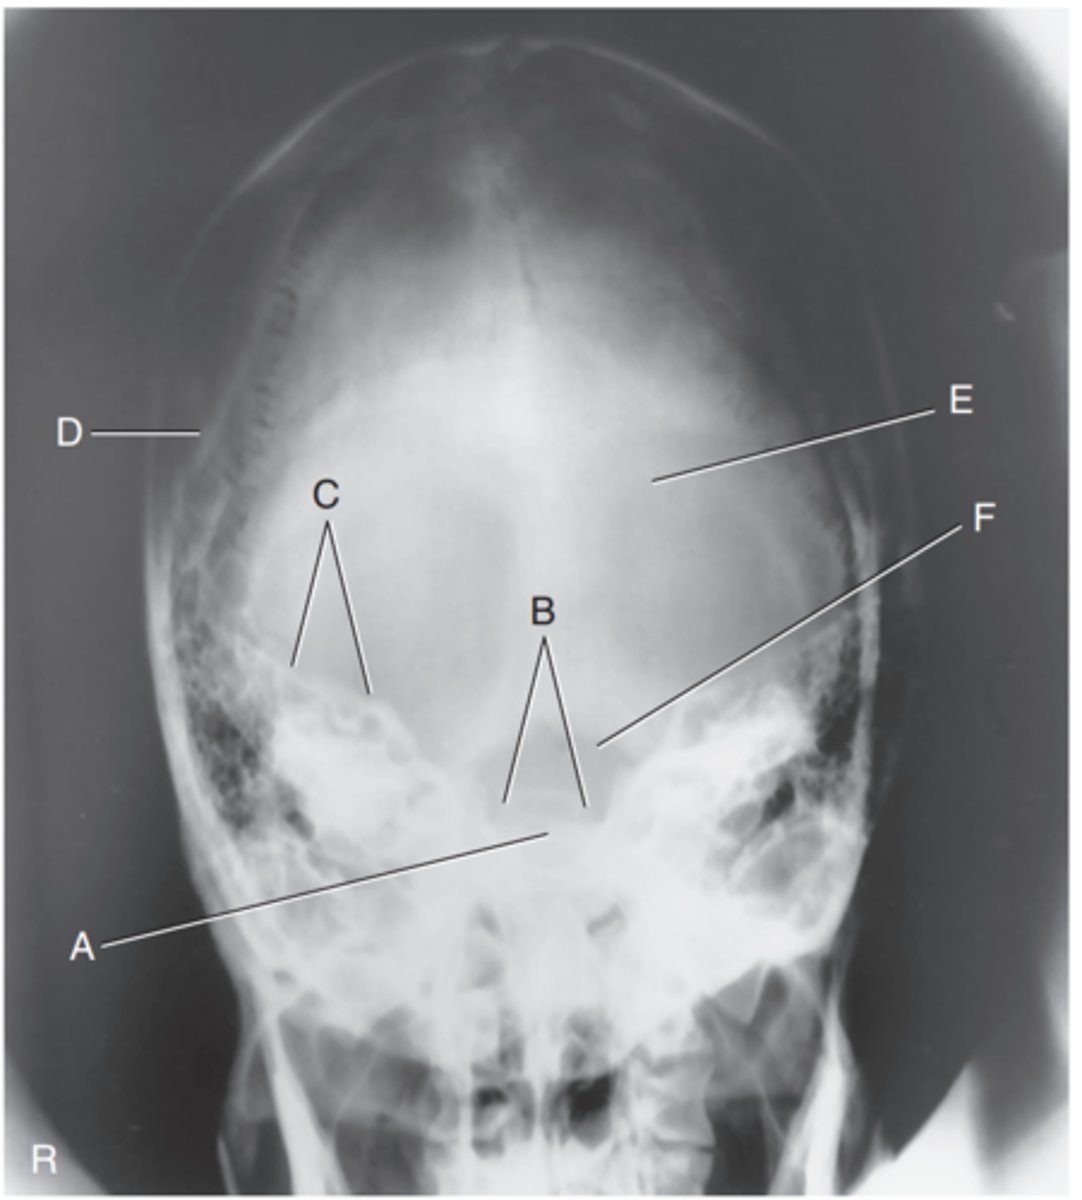

EAM

Label A

Mastoid portion of temporal bone

Label B

Occipital bone

Label C

Lambdoidal suture

Label D

Clivus

Label E

Dorsum sellae

Label F

Posterior clinoid processes

Label G

Anterior clinoid processes

Label H

Vertex of cranium

Label I

Coronal suture

Label J

Frontal bone

Label K

Orbital plates

label L

Cribriform plate

Label M

Sella turcica

Label N

Body of sphenoid (sphenoid sinus)

Label O

Petrous portion of temporal bone

Label P